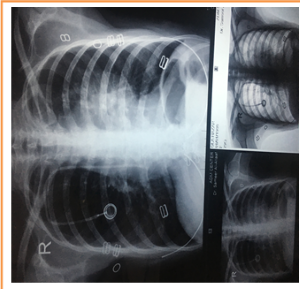

However postoperative chest X-ray was used in all cases (Figure 5); finally, skin and subcutaneous above port chamber were sutured and all wound dressing was done for the site of operation (Figure 6).